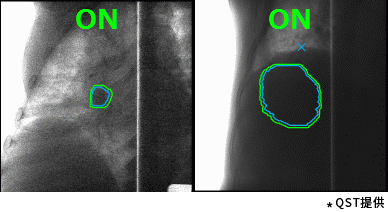

東芝的重離子癌癥放射治療系統具有高速3D掃描,患者自動(dòng)定位,小型化重離子旋轉機架(搭載東芝自研超導磁鐵實(shí)現重量和體積的大幅縮?。┑炔町惢夹g(shù)。實(shí)時(shí)成像的呼吸門(mén)控是照射技術(shù)與重復掃描技術(shù)的結合,能夠對伴隨呼吸運動(dòng)的腫瘤進(jìn)行快速、準確的照射,且保證劑量分布均一性。特別是,東芝憑借自身先進(jìn)的超導技術(shù)的加持,使旋轉機架得以逐漸小型化。這一成果直接推動(dòng)了重離子旋轉機架的商業(yè)化普及。應用旋轉機架治療,可從360度任意角度進(jìn)行照射,避開(kāi)正常組織和危及器官。治療過(guò)程中一次定位,避免了移動(dòng)患者造成的內部臟器位移,實(shí)現精準治療,同時(shí)提高治療效率,增加治療人數,在同類(lèi)型產(chǎn)品中獨具技術(shù)優(yōu)勢。

高速掃描+呼吸門(mén)控照射(動(dòng)圖)